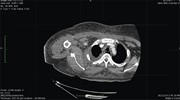

Right atrial myxoma with a large tumor embolus in the left pulmonary artery

Akihiko Ikeda and others

Journal of Surgical Case Reports, Volume 2014, Issue 10, October 2014, rju115, https://doi.org/10.1093/jscr/rju115